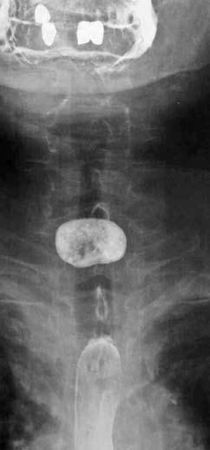

Рис. 36. Рентгенограмма пищевода при бифуркационном дивертикуле

Основным методом диагностики ДП до сих пор остается рентгенологический. Применяют контрастную рентгеноскопию и рентгенографию пищевода в разных проекциях (полипозиционное исследование). При этом определяют локализацию, размер и форму дивертикула, характер компрессии пищевода заполненным мешком. При рентгенологическом исследовании органов грудной клетки – признаки аспирационных легочных осложнений. Рентгенограммы пищевода при дивертикулах различной локализации представлены на рисунках 35–37.